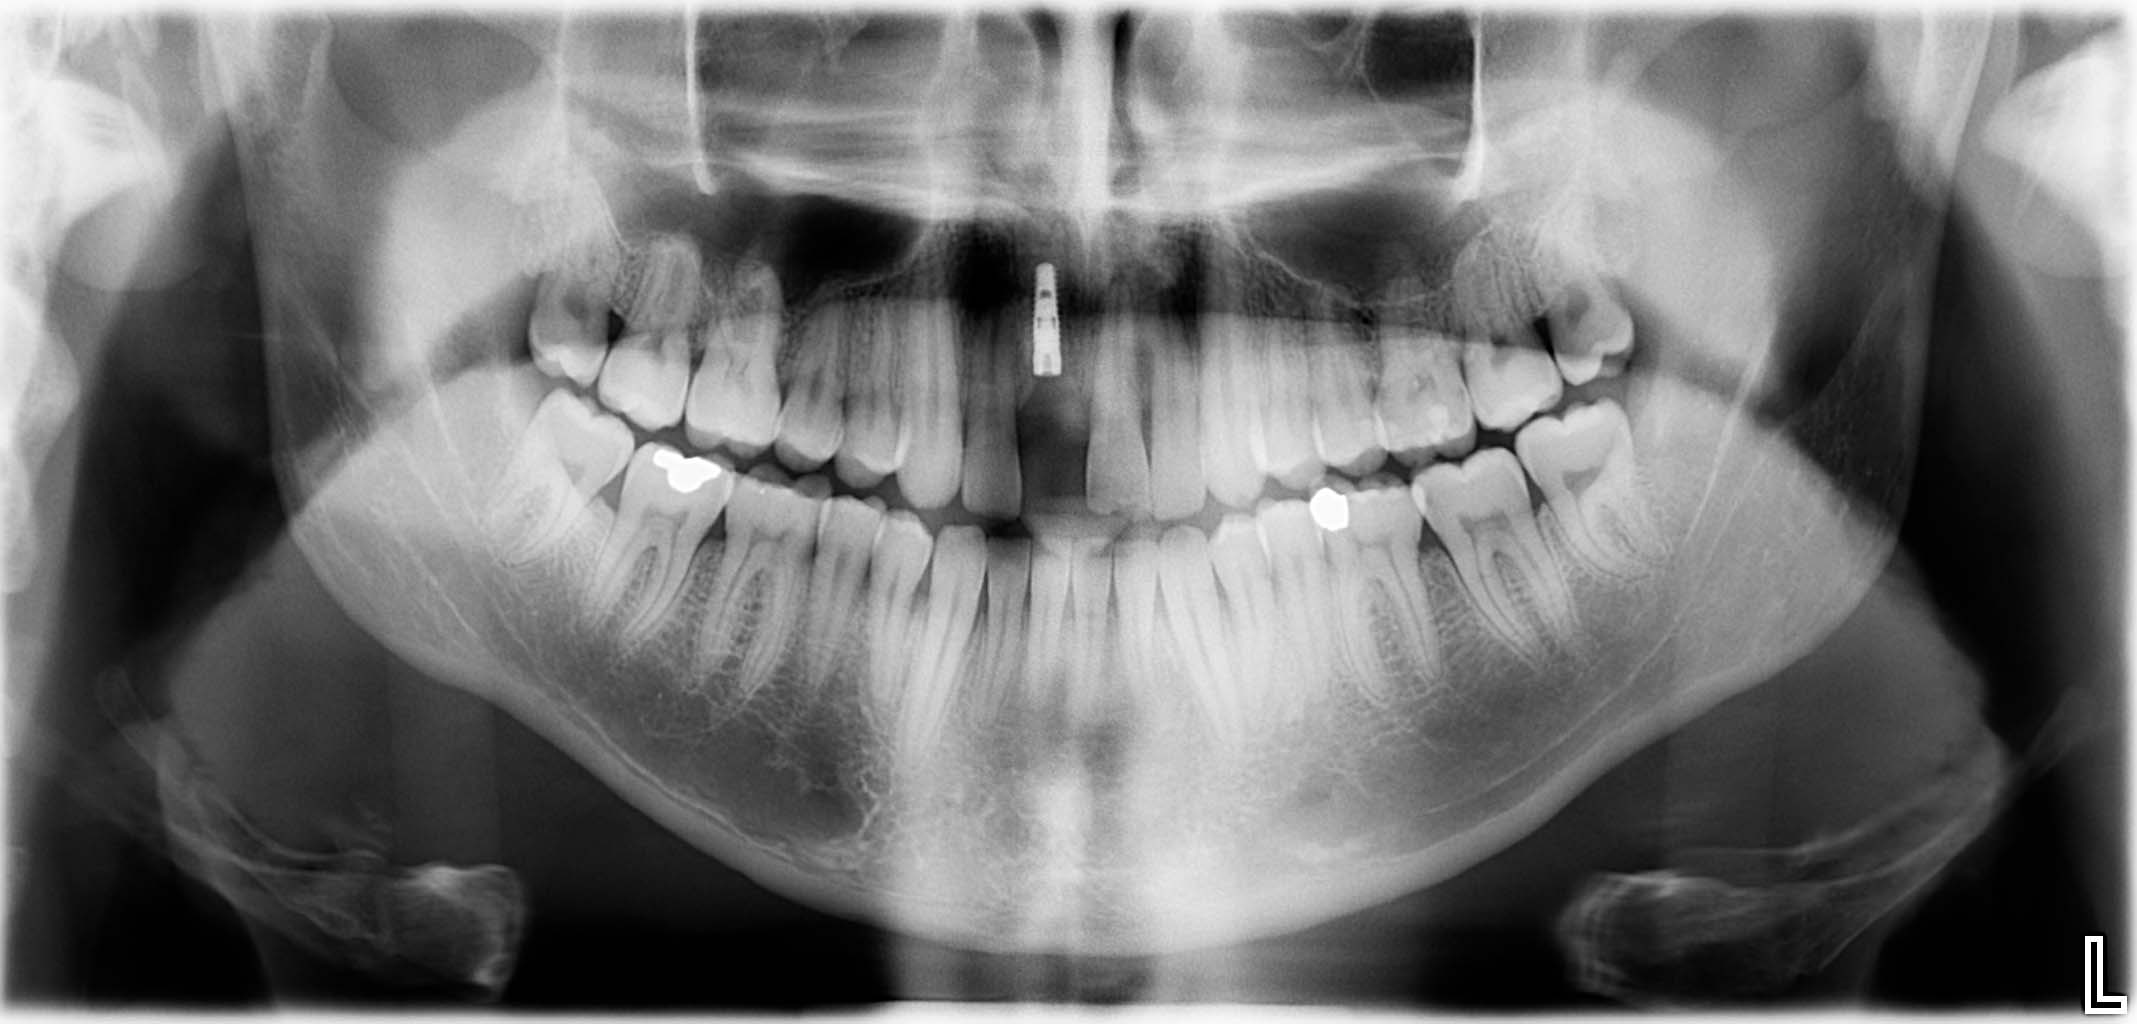

Erfolgreich implantierte Patientenfälle (klinische Fotos)